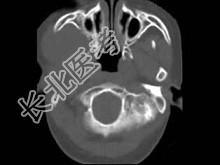

- 单项选择题男,30岁, 感右下颌部有一肿物,逐渐肿大, 胀痛,局部麻木1月余, 结合图像,最可能的诊断是 ( )

A、神经纤维瘤

B、神经鞘瘤

C、血管瘤

D、下颌骨肉瘤

E、软骨瘤